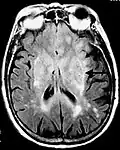

Axial fluid-attenuated inversion recovery MRI image demonstrating tumor-related infiltration involving lenticular nuclei (Arrow). -

Axial fluid-attenuated inversion recovery MRI image demonstrating tumor-related infiltration involving both temporal lobes (Short arrow), and the substantia nigra (Long arrow).